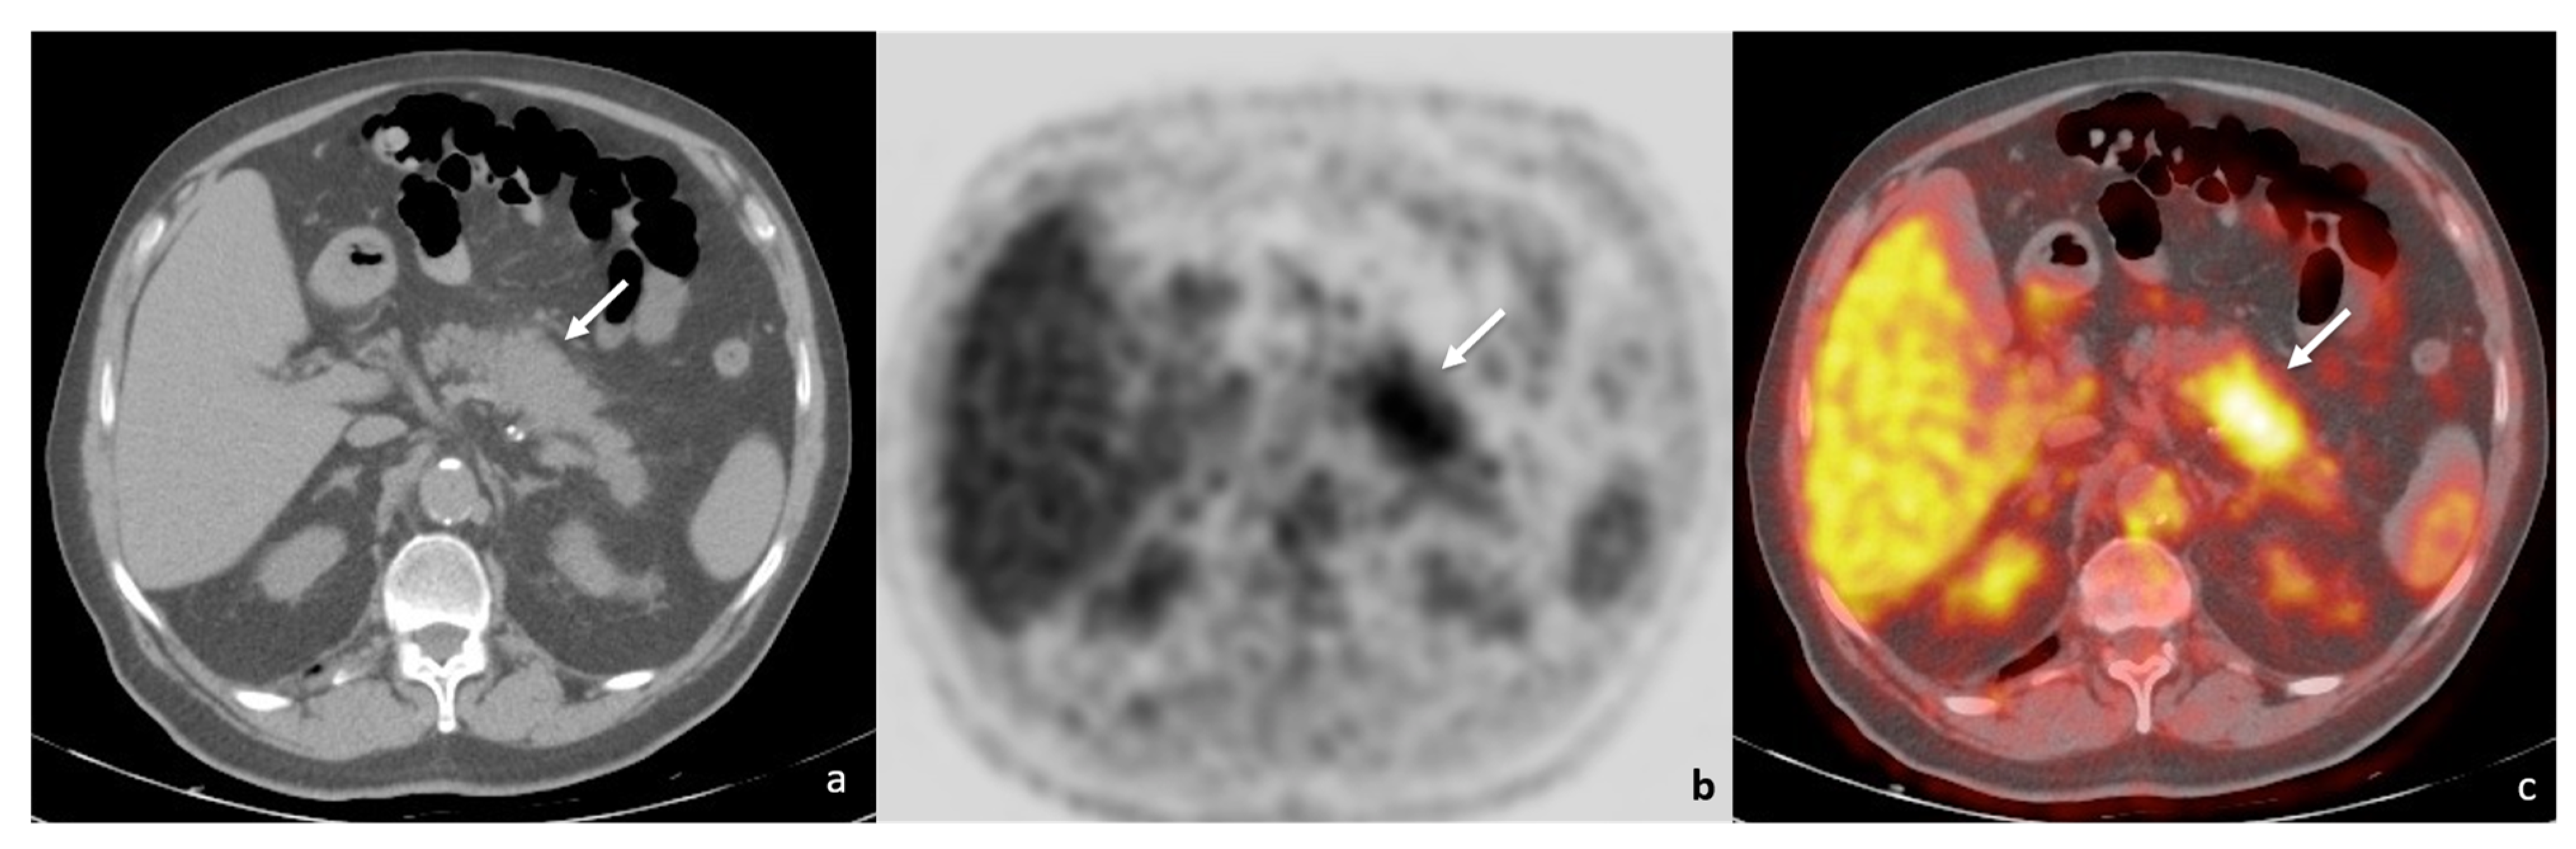

2. Case Report